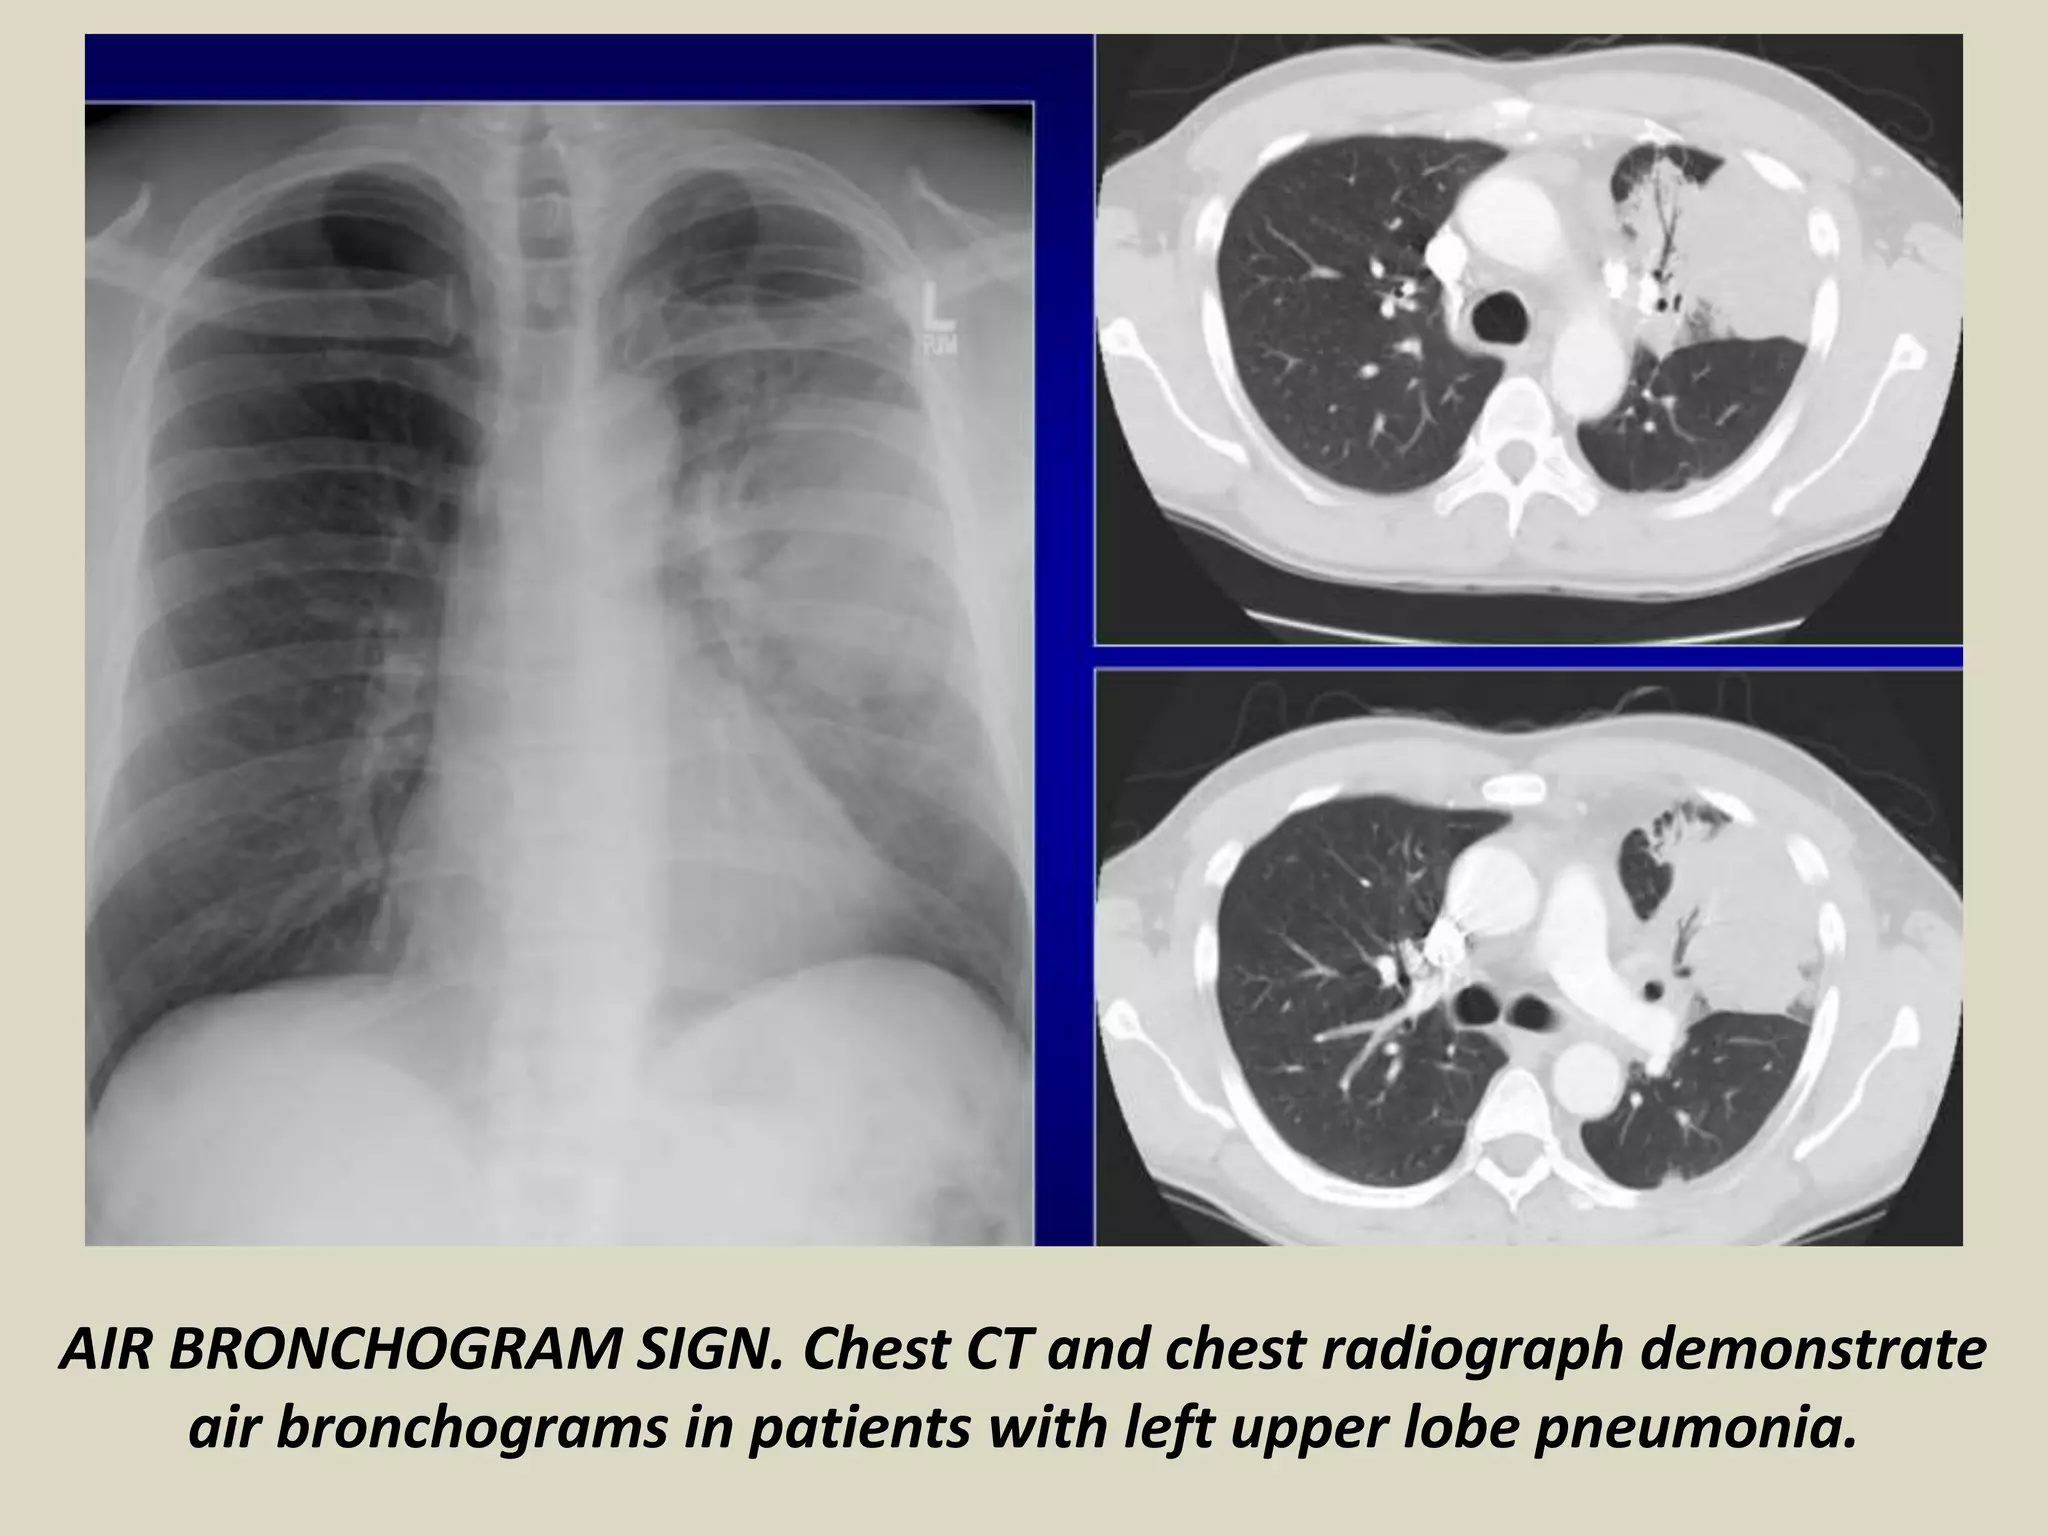

AIR BRONCHOGRAM SIGN

It occurs in infiltration or edema in tissues

adjacent to patent bronchi

Seen on chest radiographs or CT

Associated with air-space disease

It implies: patency of proximal airways,

evacuation of alveolar air by absorption

(atelectasis), replacement (pneumonia) or

both, consolidation, tumor, lymphoma.

AIR BRONCHOGRAM SIGN. Chest CT and chest radiograph demonstrate

air bronchograms in patients with left upper lobe pneumonia.

AIR BRONCHOGRAM SIGN.Chest CT and chest radiograph demonstrate air bronchograms in patients with left upper lobe pneumonia.